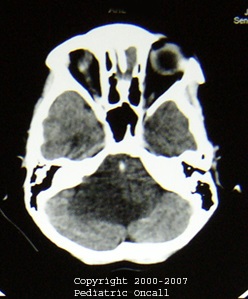

Pontine glioma

Pontine Glioma. A diffuse pontine glioma or brainstem glioma is a high-grade, or malignant, tumor. Diffuse pontine gliomas generally have a short duration (median 1 month) of symptoms prior to diagnosis, reflecting the rapid growth of these tumors. Common symptoms include cranial neuropathies, hemiparesis, hydrocephalus and raised intracranial tension. Treatment consists of radiotherapy.